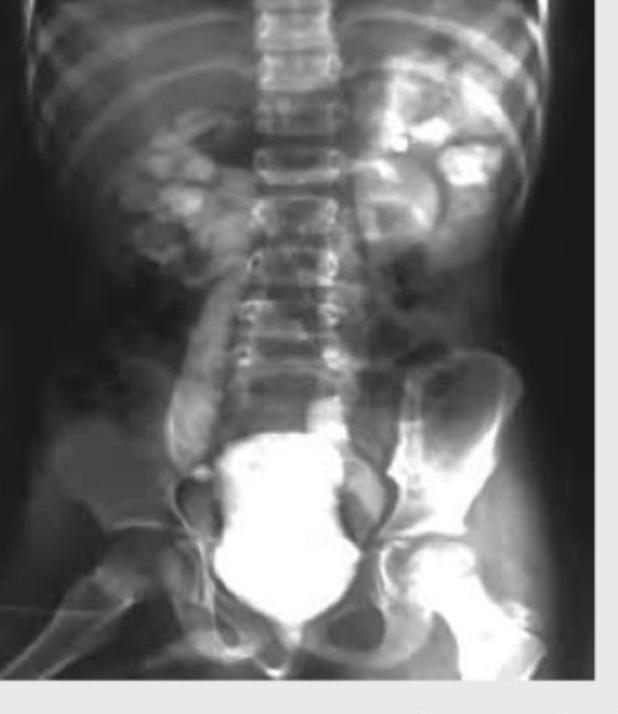

The given radiograph is diagnostic of:

Explanation: ***Correct Option: Rickets*** - The radiograph displays classic signs of **rickets**, including **widened and frayed growth plates** (physeal plates) in the long bones, particularly visible at the distal femur and wrist - Other features often seen in rickets, and suggested by the image, are **cupping and splaying of the metaphyses**, indicating defective mineralization of bone - Rickets results from vitamin D deficiency leading to impaired calcium and phosphate metabolism, causing defective bone mineralization *Incorrect Option: Scurvy* - Scurvy, due to **vitamin C deficiency**, presents with distinct radiological findings such as the **Wimberger ring sign** (opacification outlining the epiphysis) and **corner fractures** (Pelkan spurs), which are not prominently depicted - While periosteal hemorrhage can occur in scurvy, the characteristic widening and fraying of growth plates seen here are more indicative of rickets - Scurvy affects collagen formation, not mineralization like rickets *Incorrect Option: Battered baby syndrome* - Images in **battered baby syndrome** (child abuse) typically show **multiple fractures at different stages of healing**, epiphyseal separations, and metaphyseal corner fractures - These features are distinct from the bone mineralization defects characteristic of rickets, and there are no clear signs of multiple traumatic injuries - The systematic bilateral changes seen in rickets would not be typical of inflicted trauma *Incorrect Option: Osteogenesis imperfecta* - **Osteogenesis imperfecta** is characterized by extreme **bone fragility** leading to frequent fractures, often with associated blue sclerae and hearing loss - The radiographic findings would predominantly be multiple fractures and osteopenia (reduced bone density), without the specific growth plate abnormalities seen in rickets - This is a collagen disorder causing generalized bone weakness, not a mineralization disorder